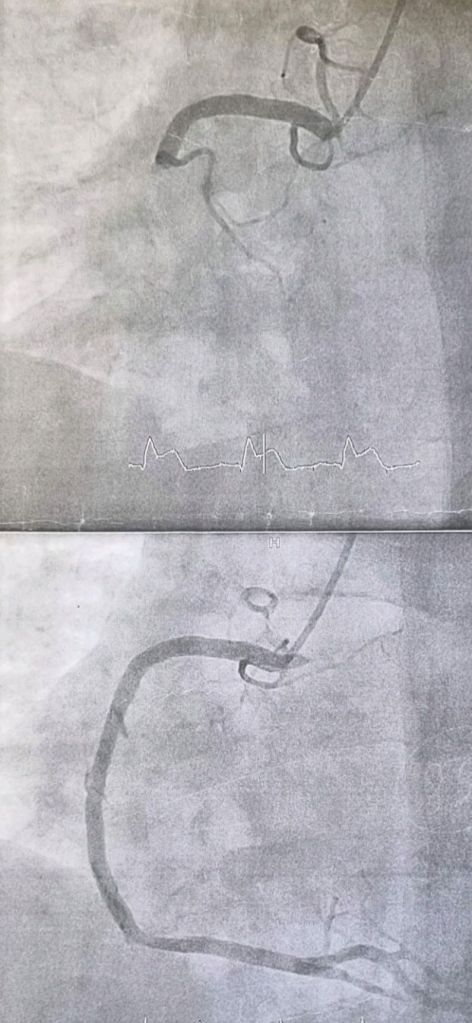

The patient was looking his heart in the monitor and after some half and hour or so, the liquid was injected in his body for the doctor to see where ONE STENT should be applied.

After some time the positioning of stent has happened and he was transfered to the hospital bed. He stayed for two nights in that hospital as doctor wanted to check how that ONE STENT worked and if the ARTERY was cured.